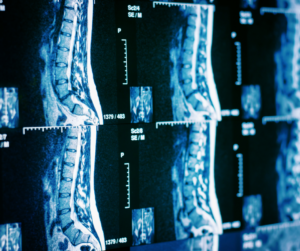

Normally when I see a patient for their initial consultation, I go through what their images show, and I go through their history from top to bottom. I tell most folks that have pain – back pain, leg pain, pinching of nerves, or instability of their back – that there are solutions for them. As a spine surgeon, I can offer surgery as an option for a lot of folks, but I try to seek out non-surgical solutions first. I think that’s what differentiates me, and Texas Orthopedics in general. I like to treat patients with as little surgery as possible. When you come to my office, I really engage, show your MRIs results, and get an understanding of your anatomical problem. When folks go through all conservative care options (injections, therapy, medications), and at the end of the day, if surgery is indicated, I offer it. I offer both open procedures and minimally invasive spine surgeries. I think when it is appropriate, patients do well with minimally invasive surgery, and they are happy with the results and getting back to the level of activity that they want to be at a quicker pace and with less pain.